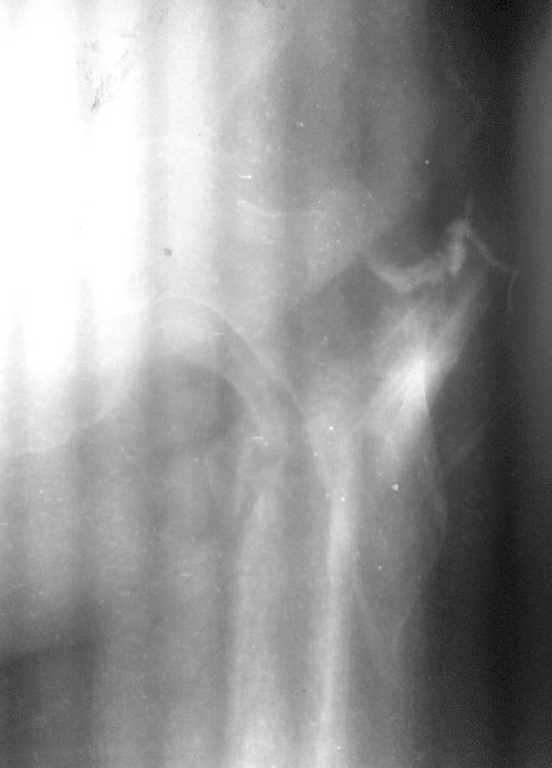

Dr Alex, добрый день. Я за двухэтапное лечение, если есть проблемы с АВФ(нежелание больной или докторов)как вариант наложить ДСВ, 2 спицы через бугристость ББК, груз 10% от массы больной, иссечь гнойный очаг и подержать до заживления.Рентген-контроль на ДСВ, если удалось растянуть по длине, то идти на закрытый синтез. Не могу разглядеть на снимках "ушел" малый вертел или нет? Если перелом из чрез-под-вертельных, то надо брать длинный гамма-гвоздь. Без ЭОПа, будет .опа, но очень интересно, 2 рентген-аппарата, лаборант бегает матерится, шейка спицами маркируется, ах молодость-молодость, приятно вспомнить.

В субботу проведна спица за бугристость ББК, вес 10 кг. Сегодня контрольные снимки - видимого удлинения в соотношении фрагментов нет, патологическая подвижность осталась. Больная тяжело переносит вынужденное положение, беспокоит боль в области перелома. Свищ с воскресенья не функционирует, признаков воспаления в проксимальном отделе бедра нет, лабораторные показатели в норме.

Малый вертел с небольшим фрагментом кортикала отломан.

Место перелома открыли, фрагменты в рубцах, каналы закрыты, кость “сахарная”

Освободили от рубцов, каналы открыли, скусили 1см острого участка проксимального фрагмента для репозиции, заштифтовали без использования молотка, заблокировали дистально 3 винтами (один винт в сагитальной плоскости) и проксимально 2 винта.